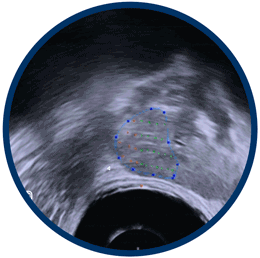

HIFUsion® Imaging

Real-time elastic fusion of MRI and Ultrasound.

We map the cancer using real-time MRI fusion imaging.